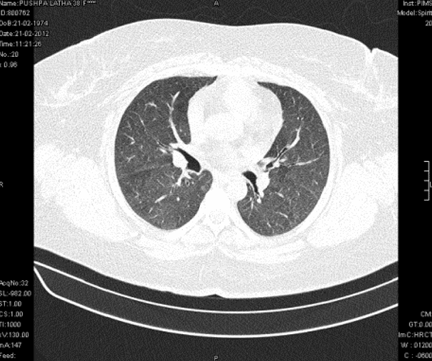

Subsequent investigations revealed corrected reticulocyte count 0.5%, microcytic hypochromic peripheral blood smear, low serum iron (36 μg/dL), low transferrin saturation (28%), normal Ferritin (140.2 ng/mL), normal total iron binding capacity (415 μg/dL) and normal serum vitamin B12 and folic acid levels. Her stool was negative for occult blood or parasites. Her serum creatinine was 0.8 mg/dL, blood urea was 36 mg/dL and urine microscopy was normal (no protein or red blood cells). The liver function tests and coagulation profile were within normal limits. Her retroviral status (HIV I and II by ELISA), hepatitis B surface antigen and hepatitis C antibody were negative. She received one pint blood transfusion in the ICU. Her chest X-ray (Figure 1) which was done in the ICU showed bilateral reticular infiltrates. Computed tomography (CT) scan of thorax was subsequently done which showed bilateral extensive ground glass opacities with interstitial thickening and nodules. (Figure 2) A provisional diagnosis of acute interstitial pneumonia/diffuse alveolar hemorrhage was made and she was started on broad spectrum antibiotics with high dose pulse steroids (Inj methylprednisolone 500 mg i.v. daily in divided doses for 3 days). Within 3 days she improved significantly and was weaned off the non invasive ventilator support. Later the steroids were tapered to oral prednisolone at 0.75 mg/kg body weight. Subsequently fibre optic bronchoscopy was done under local anesthesia with conscious sedation. Sequential broncho alveolar lavage (BAL) was done from right middle lobe, it showed increasing hemorrhagic returns of BAL aliquots and BAL counts showed 60% hemosiderophages, (Figure 3) confirming the diagnosis of diffuse alveolar hemorrhage. BAL was negative for gram stain and culture showing no evidence bacterial pathogens, acid fast bacilli, fungal organism, Fluorescent antibody stain for Pneumocystis jeroveci and cytology for cancer cells. Transbronchial lung biopsy was done from right middle and lower lobes. It showed interstitial fibrosis, hemosiderin laden macrophages in alveolar spaces and interstitium with positive Perl’s stain. (Figure 4) There was no evidence of vasculitis (capillaritis), granulomas, organising pneumonia and malignancy in the biopsy specimen. Her serum Rheumatoid factor (RF), antinuclear antibody (ANA), Double stranded Deoxyribonucleic acid (DsDNA), antiphospholipid antibody(APLA), Anti Glomerular Basement Membrane antibody (anti GBM) and anti U1 RNP were negative. Serum Complements (C3, C4 and Total Complement) and Antineutrophilic Cytoplasmic antibodies(c and p ANCA) were in normal range. After one week of treatment with steroids, she improved and there was no further drop in hemoglobin. At this time spirometry was done and it was normal. Her chest X-ray and CT thorax repeated after one month showed complete clearing of the shadows. (Figure 5)

Figure 1: Chest X-ray showing diffuse reticulo nodular shadows involving all segments of both lung fields. X-ray done at the time of admission when the patient was in acute respiratory failure.